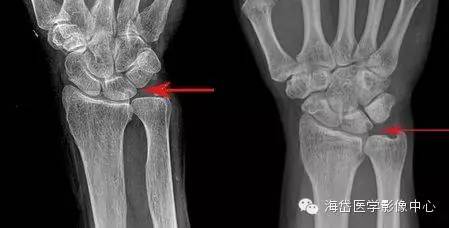

①X线:尺骨阳性变异(尺骨远端伸长)或处于中立位;月骨、三角骨坏死呈低密度小囊状改变以及月骨、三角骨关节面下软骨硬化,病变部位位于月骨尺侧近端和三角骨的腰部;尺骨小头相对关节面下软骨硬化或小囊性变。

其他X线表现包括桡骨远端骨折畸形愈合,桡骨远端异常背倾畸形和桡骨近端骨折畸形愈合导致桡骨缩短,尺桡远侧关节脱位。因为尺骨头与月骨解剖位置邻近,易发生撞击且易形成桥连状态(尺骨头与月骨连接)而产生持久性压迫,因此在尺骨阳性变异的患者中月骨发病率明显大于三角骨。

X线测量:在标准后前位X线平片测量尺骨变异,采用Gelberman等的平行线法(尺骨头关节面的平行线与乙状切迹最远端关节面的平行线之间的位置距离差)。

尺骨头长于桡骨为阳性变异; 尺骨头短于桡骨为阴性变异; 两者相等为中性变异。

对症状较重者、常规X线后前位显示尺骨变异呈阴性或中性者,采用握拳、腕旋前位摄片。